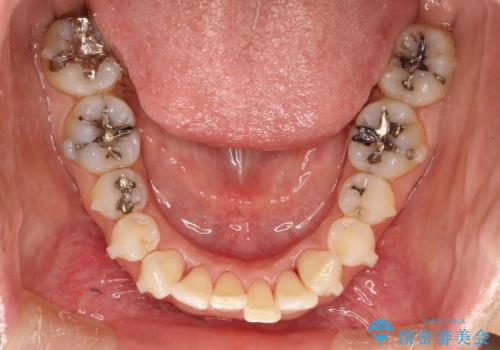

- 前歯のがたつきを気にされて来院されました。

右上の前から2番目の歯が前方に大きく傾いており、下の前歯もガタガタしていました。

インビザラインにて、歯と歯のあいだをわずかに削り並べる計画としました。